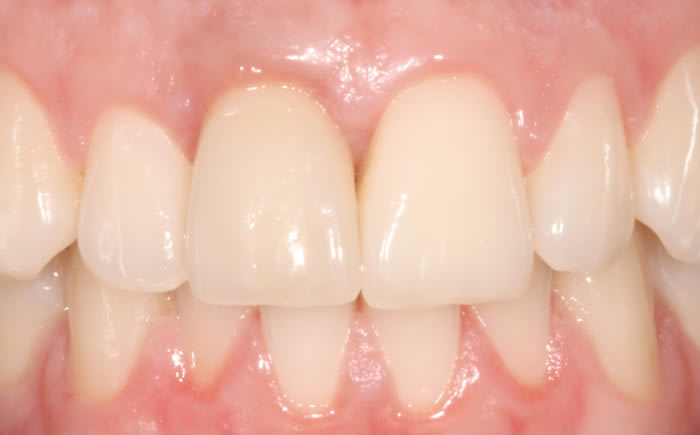

Before & After Gallery

More front teeth replaced by dental implants

Case Three (4 images)